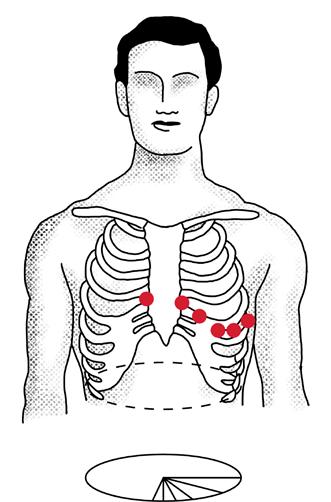

HNE: Roði í slímhimnu (conjunctiva) og hvítu (sclera) sem náði ekki að glærubrún (mynd 1A). Þroti í kringum augu en enginn gröftur. Ekki hor í nösum eða roði í hálsi en lítil blaðra á innanverðri kinn hægra megin. Varir þrútnar, rauðar, þurrar og sprungnar (mynd 1B).Hvít skán á bólginni tungu (mynd 1C).Eitlastækkanir beggja vegna á hálsi. Hjarta og lungu:Hjartahlustun eðlileg.Radialis púlsar sterkir og reglulegir. Lungnahlustun hrein.Góð háræðafylling.  Kviður: Mjúkur og eymslalaus. Húð: Mikið af rauðum blettóttum útbrotum ílófumogáiljumþarsemþauvorueinnigorðin samfelld (confluent) (mynd 1D). Hringlaga og markskífulaga (targetoid) ljósrauð blettótt útbrot á bringu, baki, fótleggjum og kvið og í holhönd og nára. Mismunandi að stærð frá nokkrum mm uppí 2-3 cm.

Mynd 1. Einkenni við komu á bráðamóttöku. (A) Roði í slímhimnu og hvítu sem náði ekki að glærubrún. (B) Þurrar og sprungnar varir. (C)

Hvít skán á bólginni tungu. (D) Blettótt, samfelld, markskífulaga útbrot.